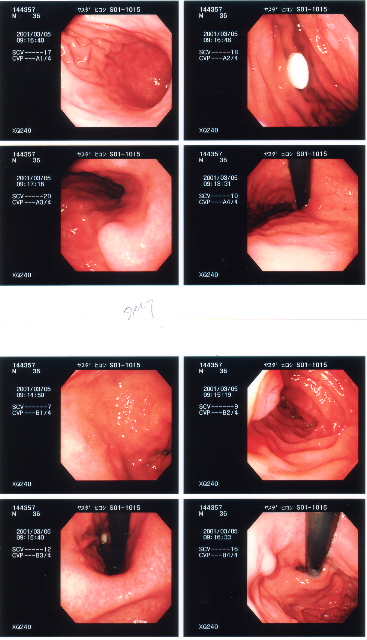

2001/3/5 胃カメラ 潰瘍などはないが、胃の入り口付近に瘤がある。

筋腫または水の可能性が高いが、超音波による検査が必要との事。